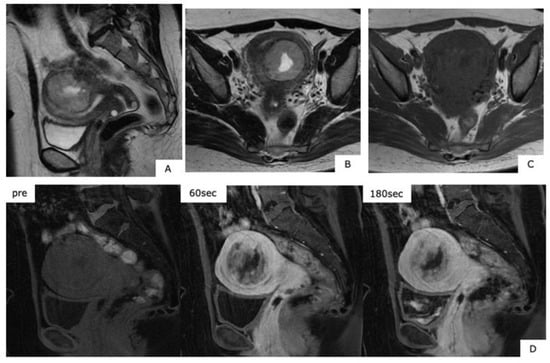

Figure 6.

Magnetic resonance images of low-grade endometrial stromal sarcoma (age, 41 years). (A): T2-weighted sagittal section, (B): T1-weighted axial section, (C): T1-weighted axial section, (D): dynamic MRI contrast sagittal section. Within the uterine posterior wall myometrium, in T2-weighted images, there are mild high signals, with slow deep dyeing in the dynamic contrast-enhanced magnetic resonance imaging, with a finding of mass accompanied with internal necrosis. The T1-weighted images of C present faint high signals.